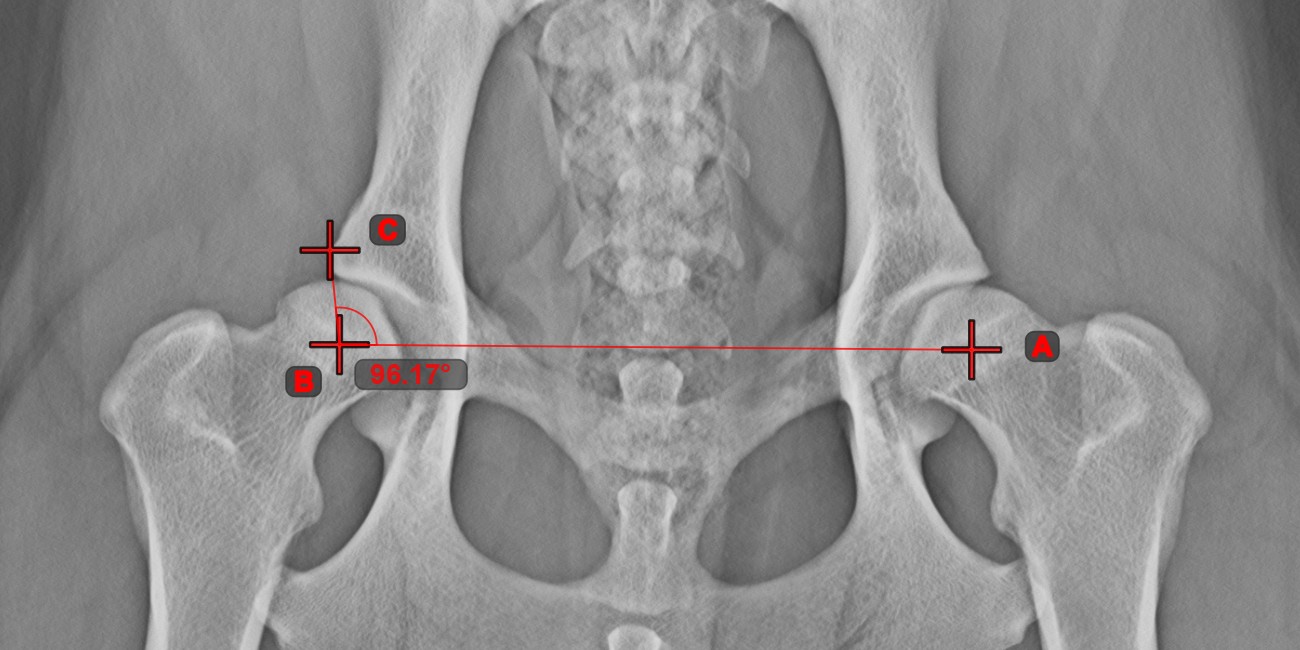

Angle of Lines¶

Select the tool from the left toolbar and assign it to one of the available mouse buttons. Start by selecting the first line from the ones already drawn on the scene, or place the start and end points to create the line. Follow the same steps for the second line of the measurement. The angle between the two lines will be automatically calculated.

Modify the start and end points of both lines by using the Select/Move Item

tool. The angle between the two lines will be automatically recalculated.

Information

If two lines do not intersect directly, the angle of their extended projections on the scene will be calculated.